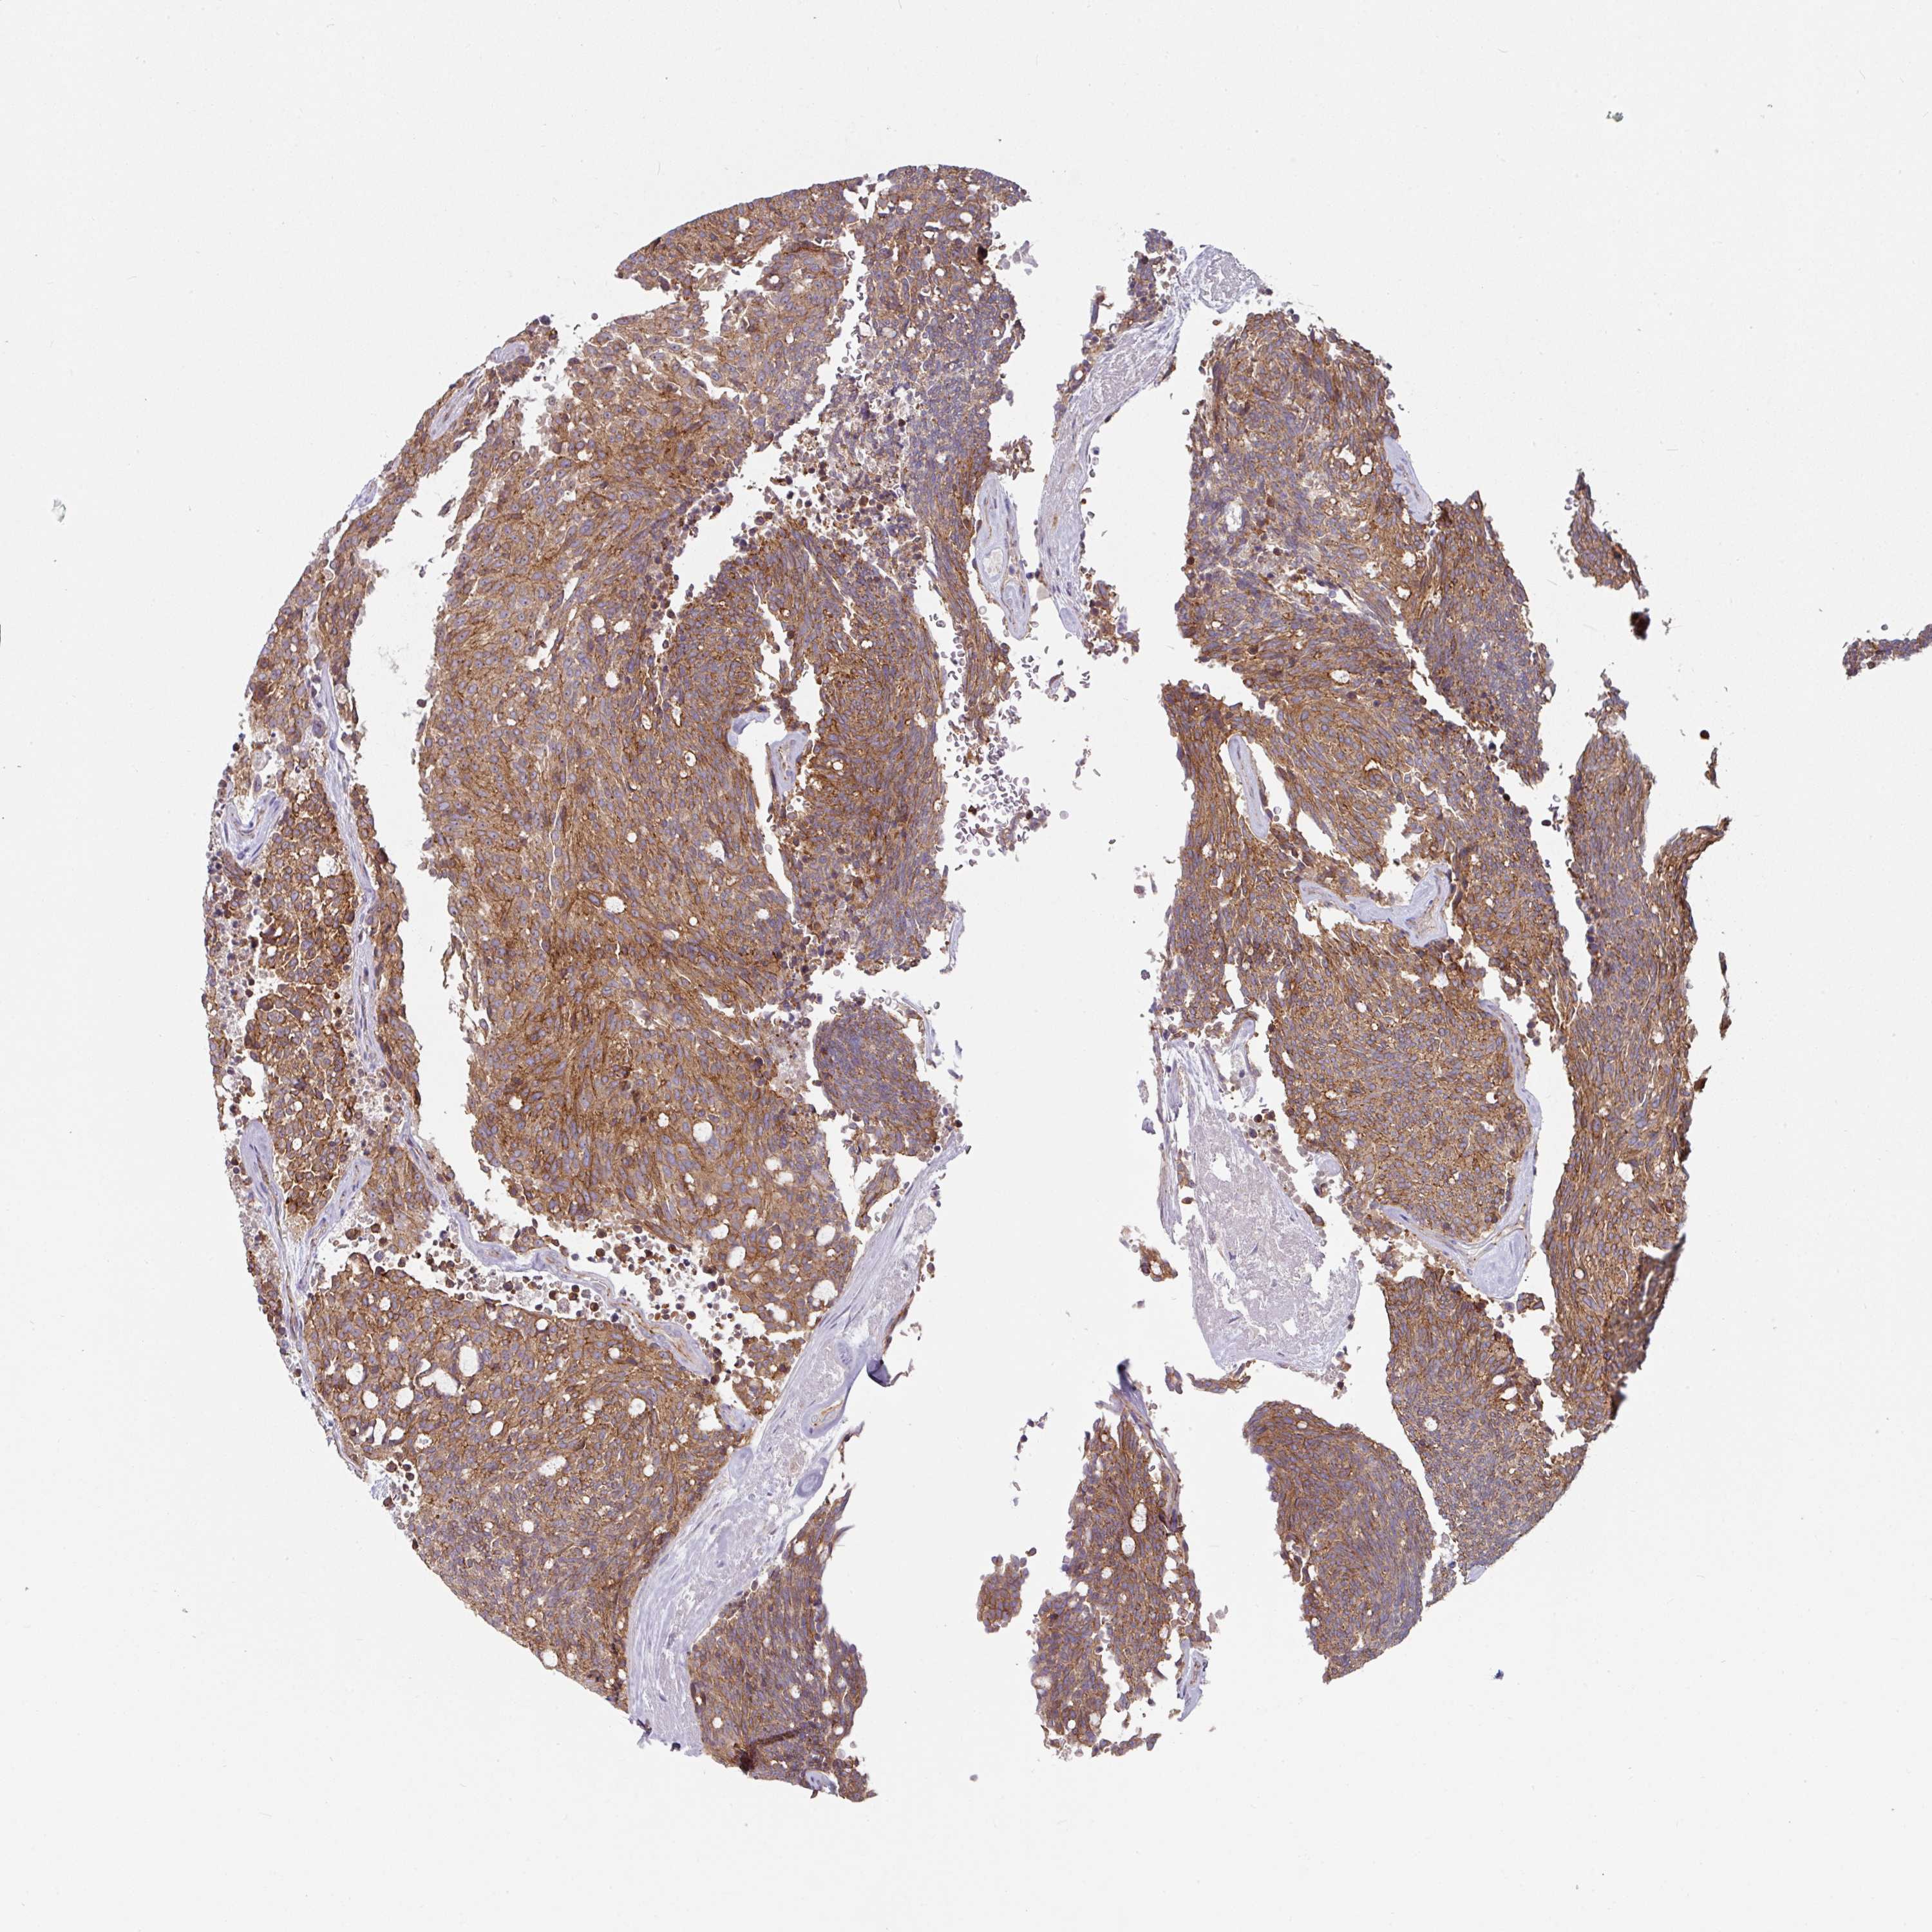

CARCINOID - Protein expressioni

A mouse-over function shows sample information and annotation data. Click on an image to view it in a full screen mode. Samples can be filtered based on level of antibody staining by selecting one or several of the following categories: high, medium, low and not detected. The assay and annotation is described here.

Each image is clickable and will lead to virtual microscopy that enables deeper exploration of all samples and also displays staining intensity scores, fraction scores and subcellular localization as well as patient and tissue information for each sample.

Antibody HPA032047

Antibody CAB002139

Staining

High

Medium

Low

Not detected

Intensity

Strong

Moderate

Weak

Negative

Quantity

>75%

75%-25%

<25%

None

Location

Nuclear

Cytoplasmic/membranous

Cytoplasmic/membranous,nuclear

Carcinoid, malignant, NOS